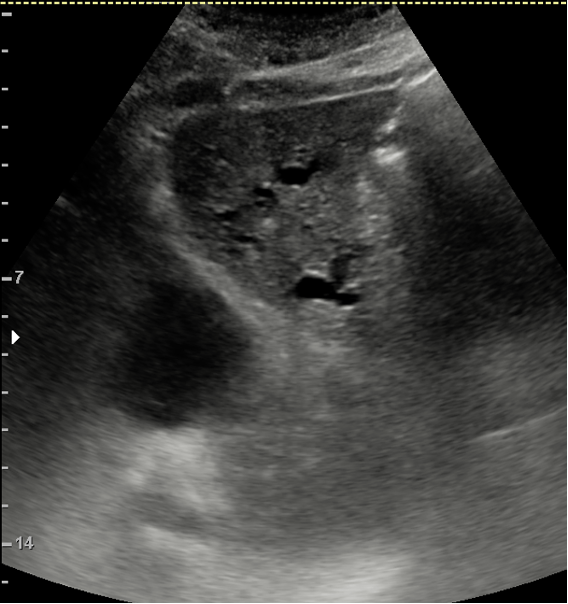

Hallazgos ecográficos

JC: Tumor páncreas.

Diagnóstico definitivo: Adenocarcinoma de cabeza de páncreas cT1c cN0 cM0 KRAS G12D.